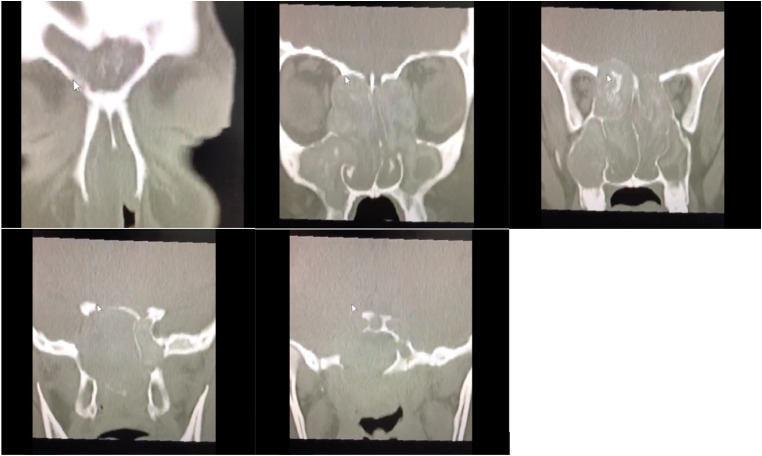

Allergic fungal rhinosinusitis (AFRS) is a subtype of chronic noninvasive sinusitis accounting for 7.8% (0.2%-26.7%) of all chronic rhinosinusitis cases. A definitive diagnosis is usually made after sinus surgery. Successful treatment requires a combination of surgical and medical management. Although orbital involvement is relatively common, reports on optic neuropathy and acute vision loss are limited. Herein, we present a series of 3 patients with AFRS who presented with acute visual loss as the chief complaint. All 3 patients were otherwise healthy adults in their early 20s with extensive nasal polyps on endoscopic nasal examination and bone erosion in the bilateral orbits and lateral wall of the sphenoid sinus on the affected side on imaging. One of the 3 patients had bilateral cranial nerve IV defects in addition to cranial nerve III defects. All patients underwent endoscopic sinus surgery with orbital decompression and were followed up postoperatively by both otolaryngology and ophthalmology services with endoscopic and radiologic evaluation. Unfortunately, no meaningful improvement in vision was observed in any patient despite successful nerve decompression. Prompt diagnosis and early medical and surgical intervention are warranted to prevent complications in patients with AFRS with orbital extension.

Abstract Image